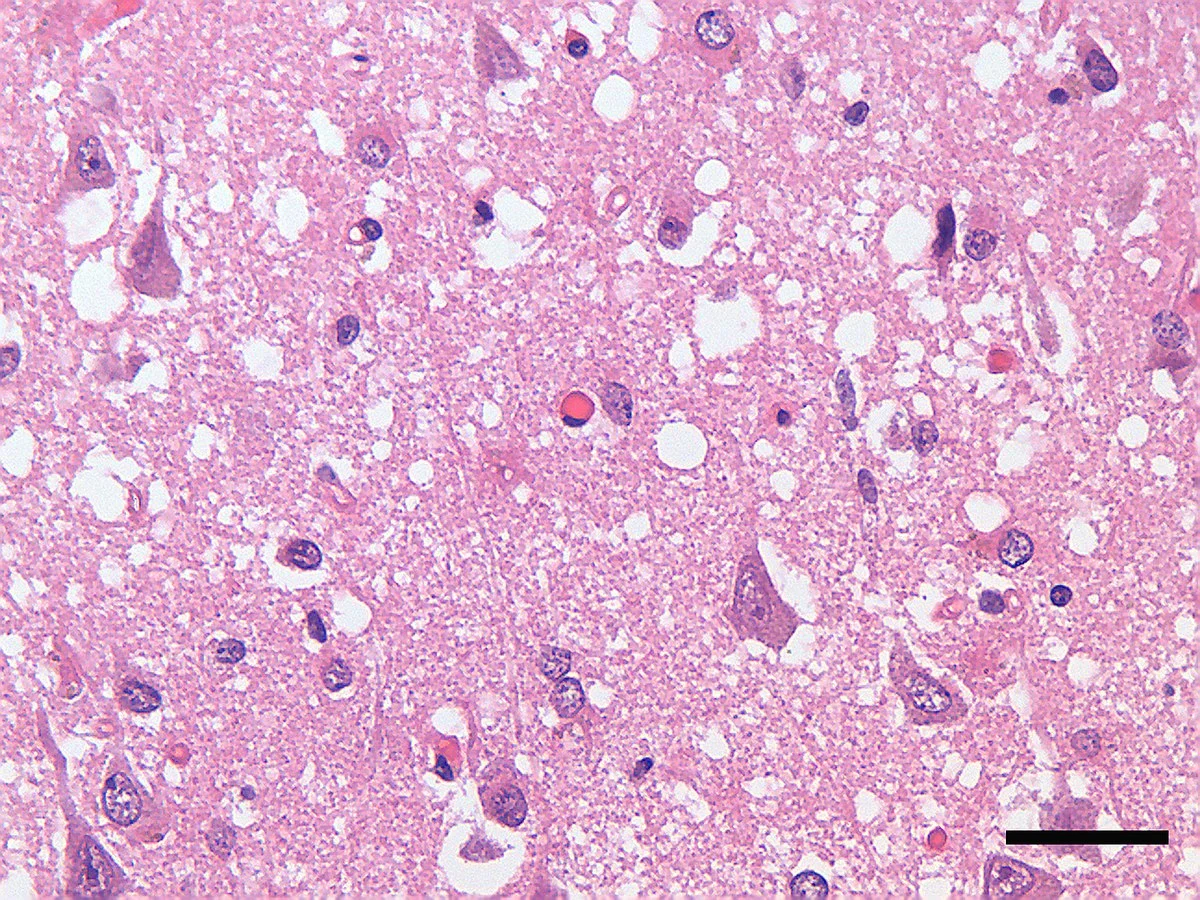

SCP-008 프리온 감염 뇌 조직 - 해면상 변성이 관찰되는 현미경 사진

프리온에 감염된 뇌 조직의 현미경 사진. 조직이 스펀지처럼 구멍이 뚫려 있다. SCP-008 감염자의 뇌에서도 유사한 변성이 관찰된다고 한다.